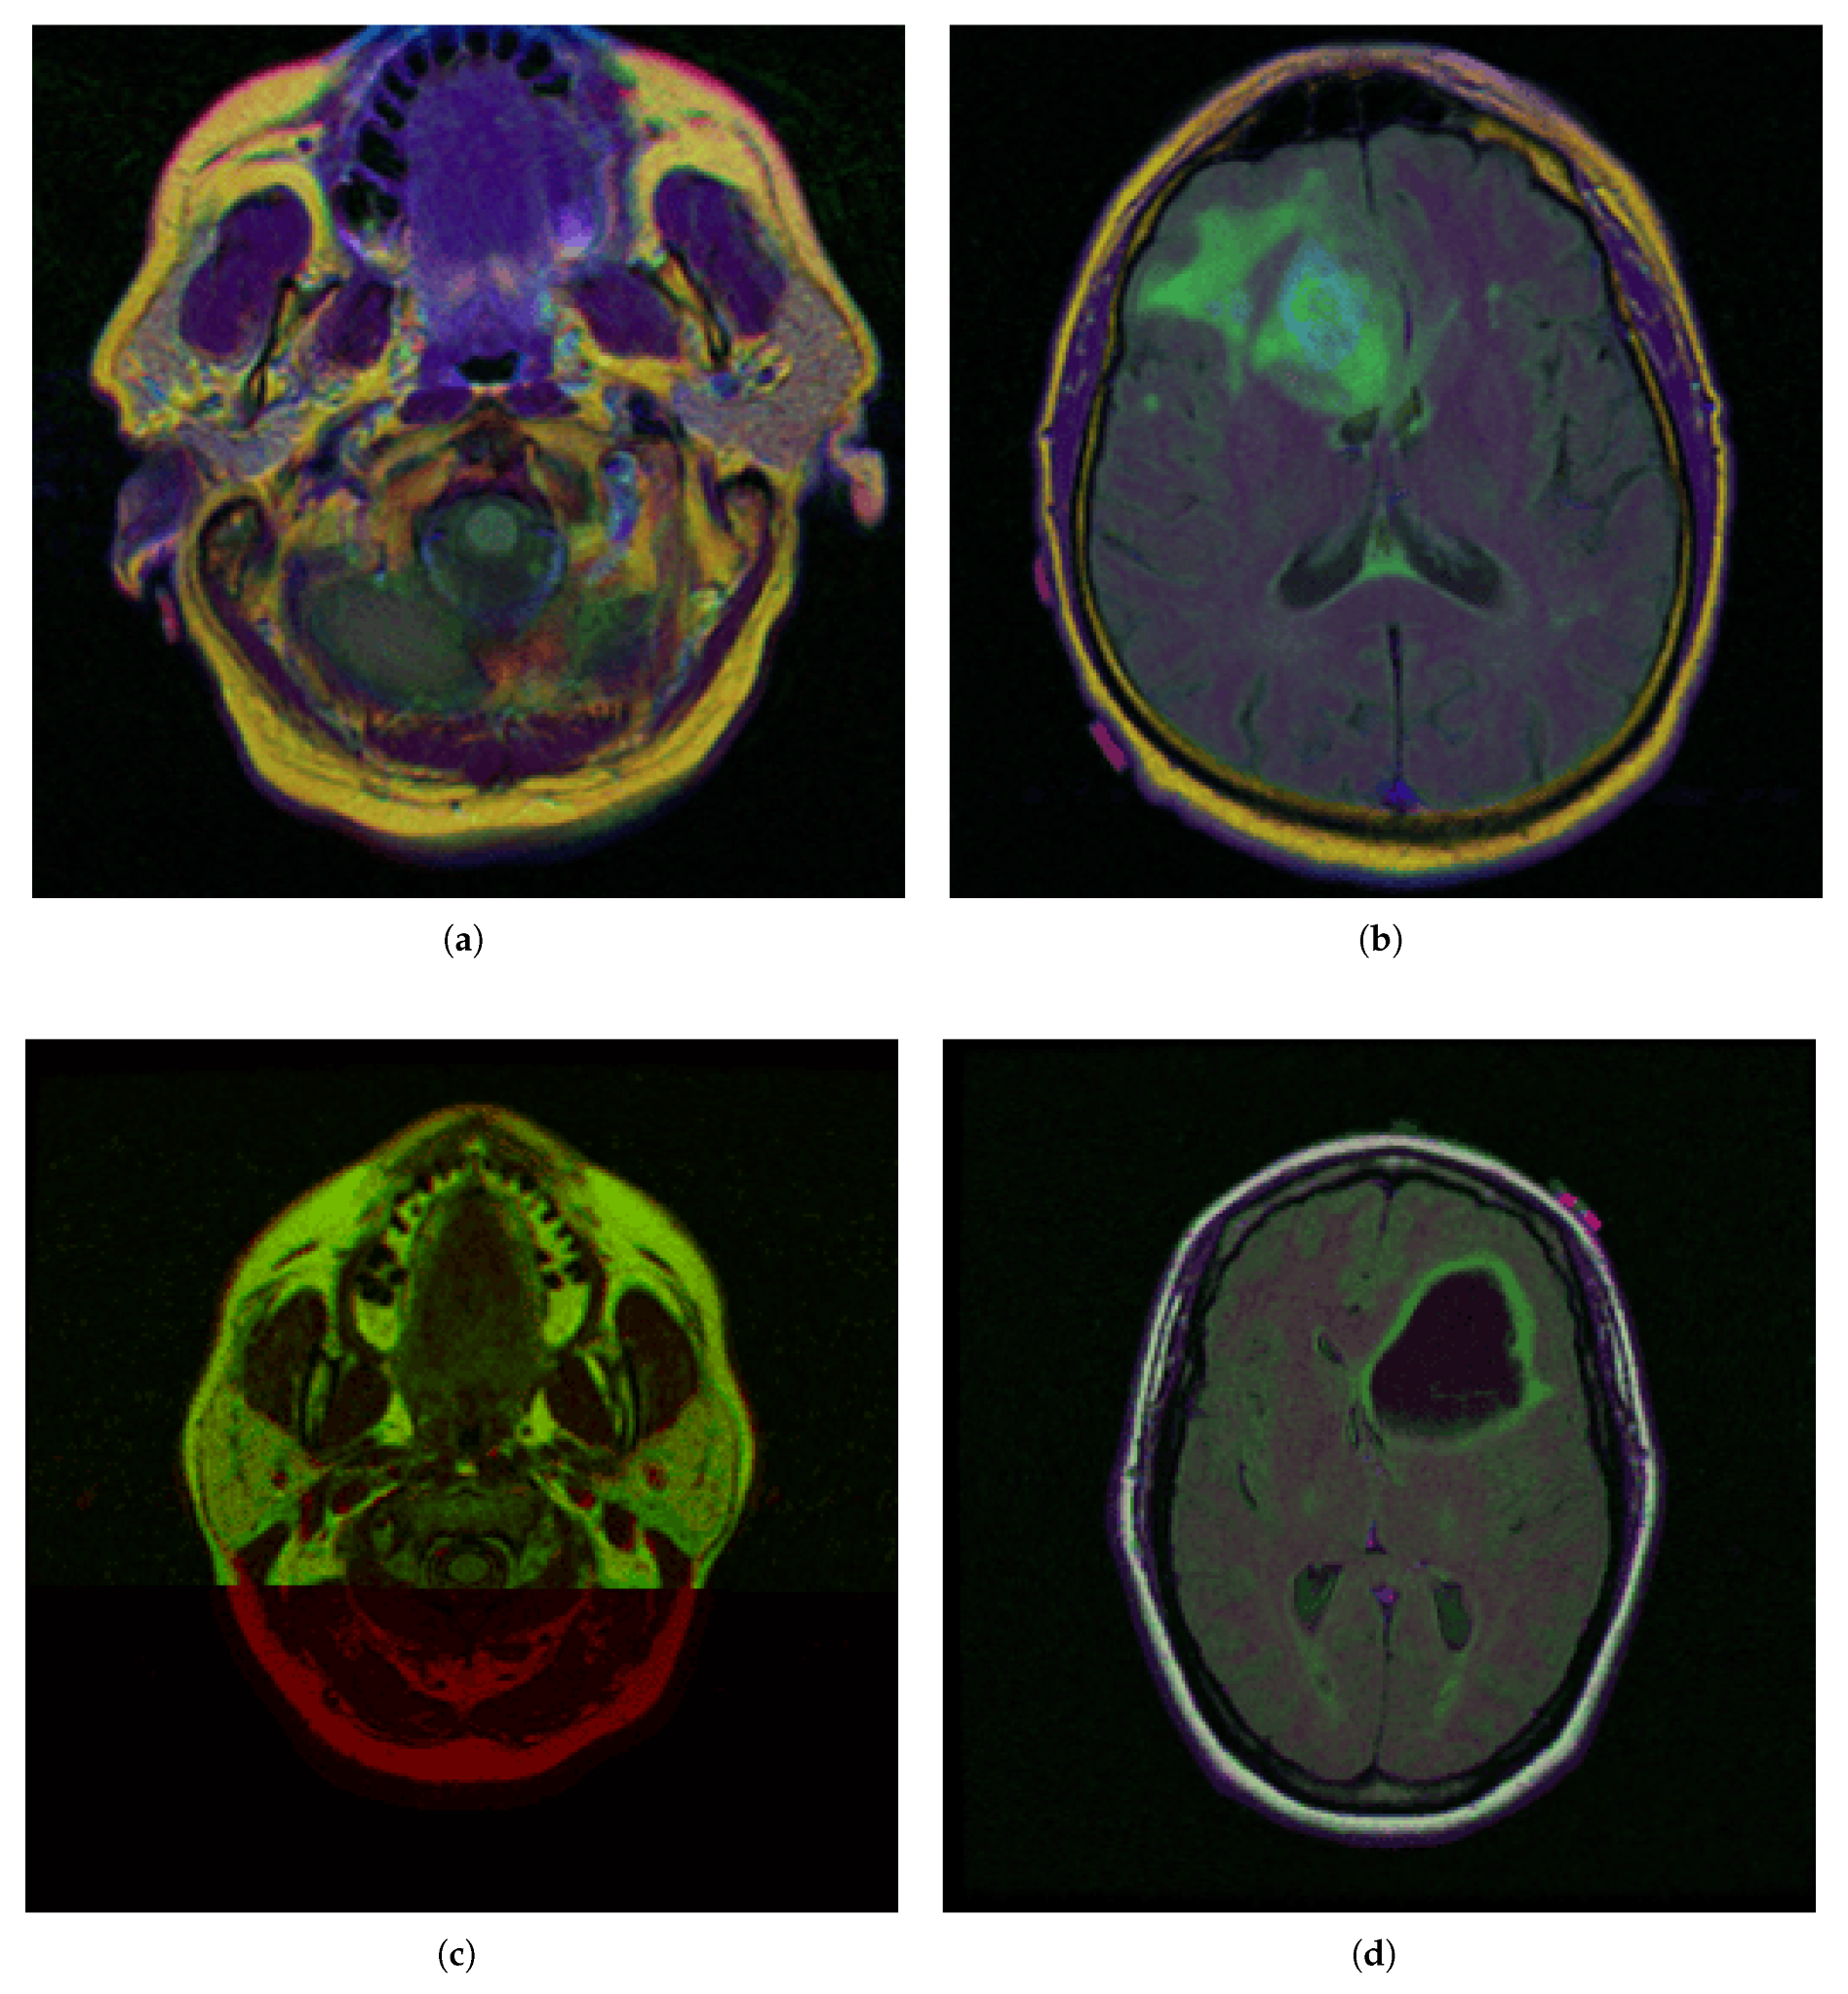

- Red (255, 0, 0)—Tumor core (non-enhancing tumor + necrotic core)

- Green (0, 255, 0)—Edema (swelling around the tumor)

- Blue (0, 0, 255)—Enhancing tumor (region showing contrast enhancement)